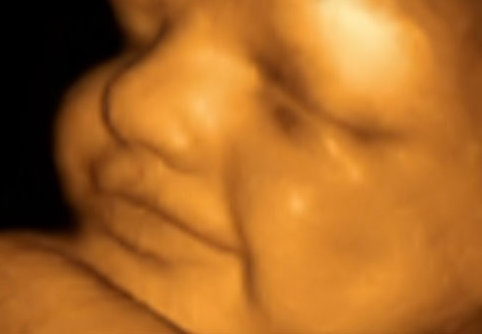

Hình ảnh siêu âm màu 4D:

Siêu âm màu 4D cho hình ảnh thai nhi rõ nét

Siêu âm là phương pháp chẩn đoán hình ảnh an toàn, không gây hại đến sức khỏe của người bệnh. Đặc biệt, kỹ thuật siêu âm 4D cung cấp cho khách hàng những hình ảnh sắc nét, sống động và vô cùng chính xác. Các dịch vụ siêu âm tại khoa Chẩn đoán hình ảnh của Bệnh viện đa khoa Quang Khởi gồm có: Siêu âm tuyến giáp, siêu âm tổng quan ổ bụng, siêu âm tuyến vú, siêu âm phần phụ, tiền liệt tuyến, siêu âm rụng trứng, siêu âm tổ chức phần mềm, Doppler mạch ngoại bên và tứ chi,...